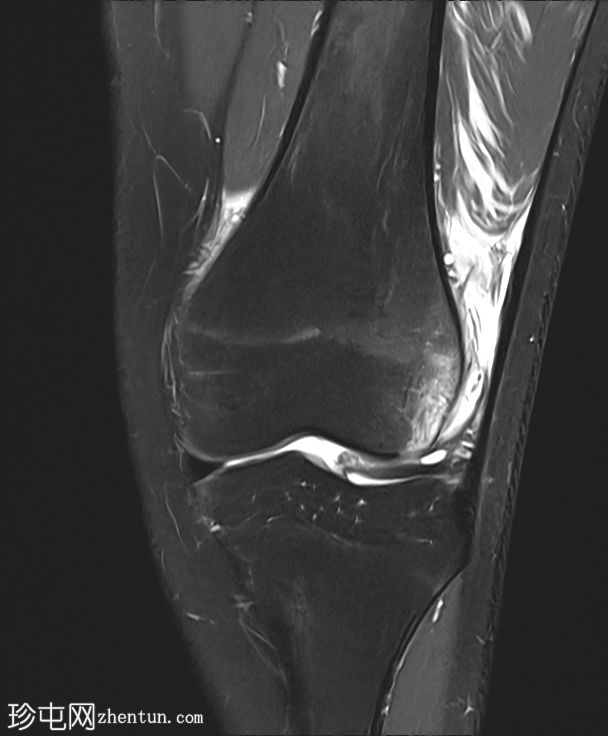

矢状位

T1加权像

内侧髌股韧带撕裂,伴外侧髌骨半脱位。

内侧髌骨缘可见骨髓水肿和一小块皮质撕脱碎片,内侧髌骨关节面存在全层软骨缺损。

外侧股骨髁轻度骨髓水肿。

内侧副韧带和外侧副韧带II级损伤。

膝关节积液